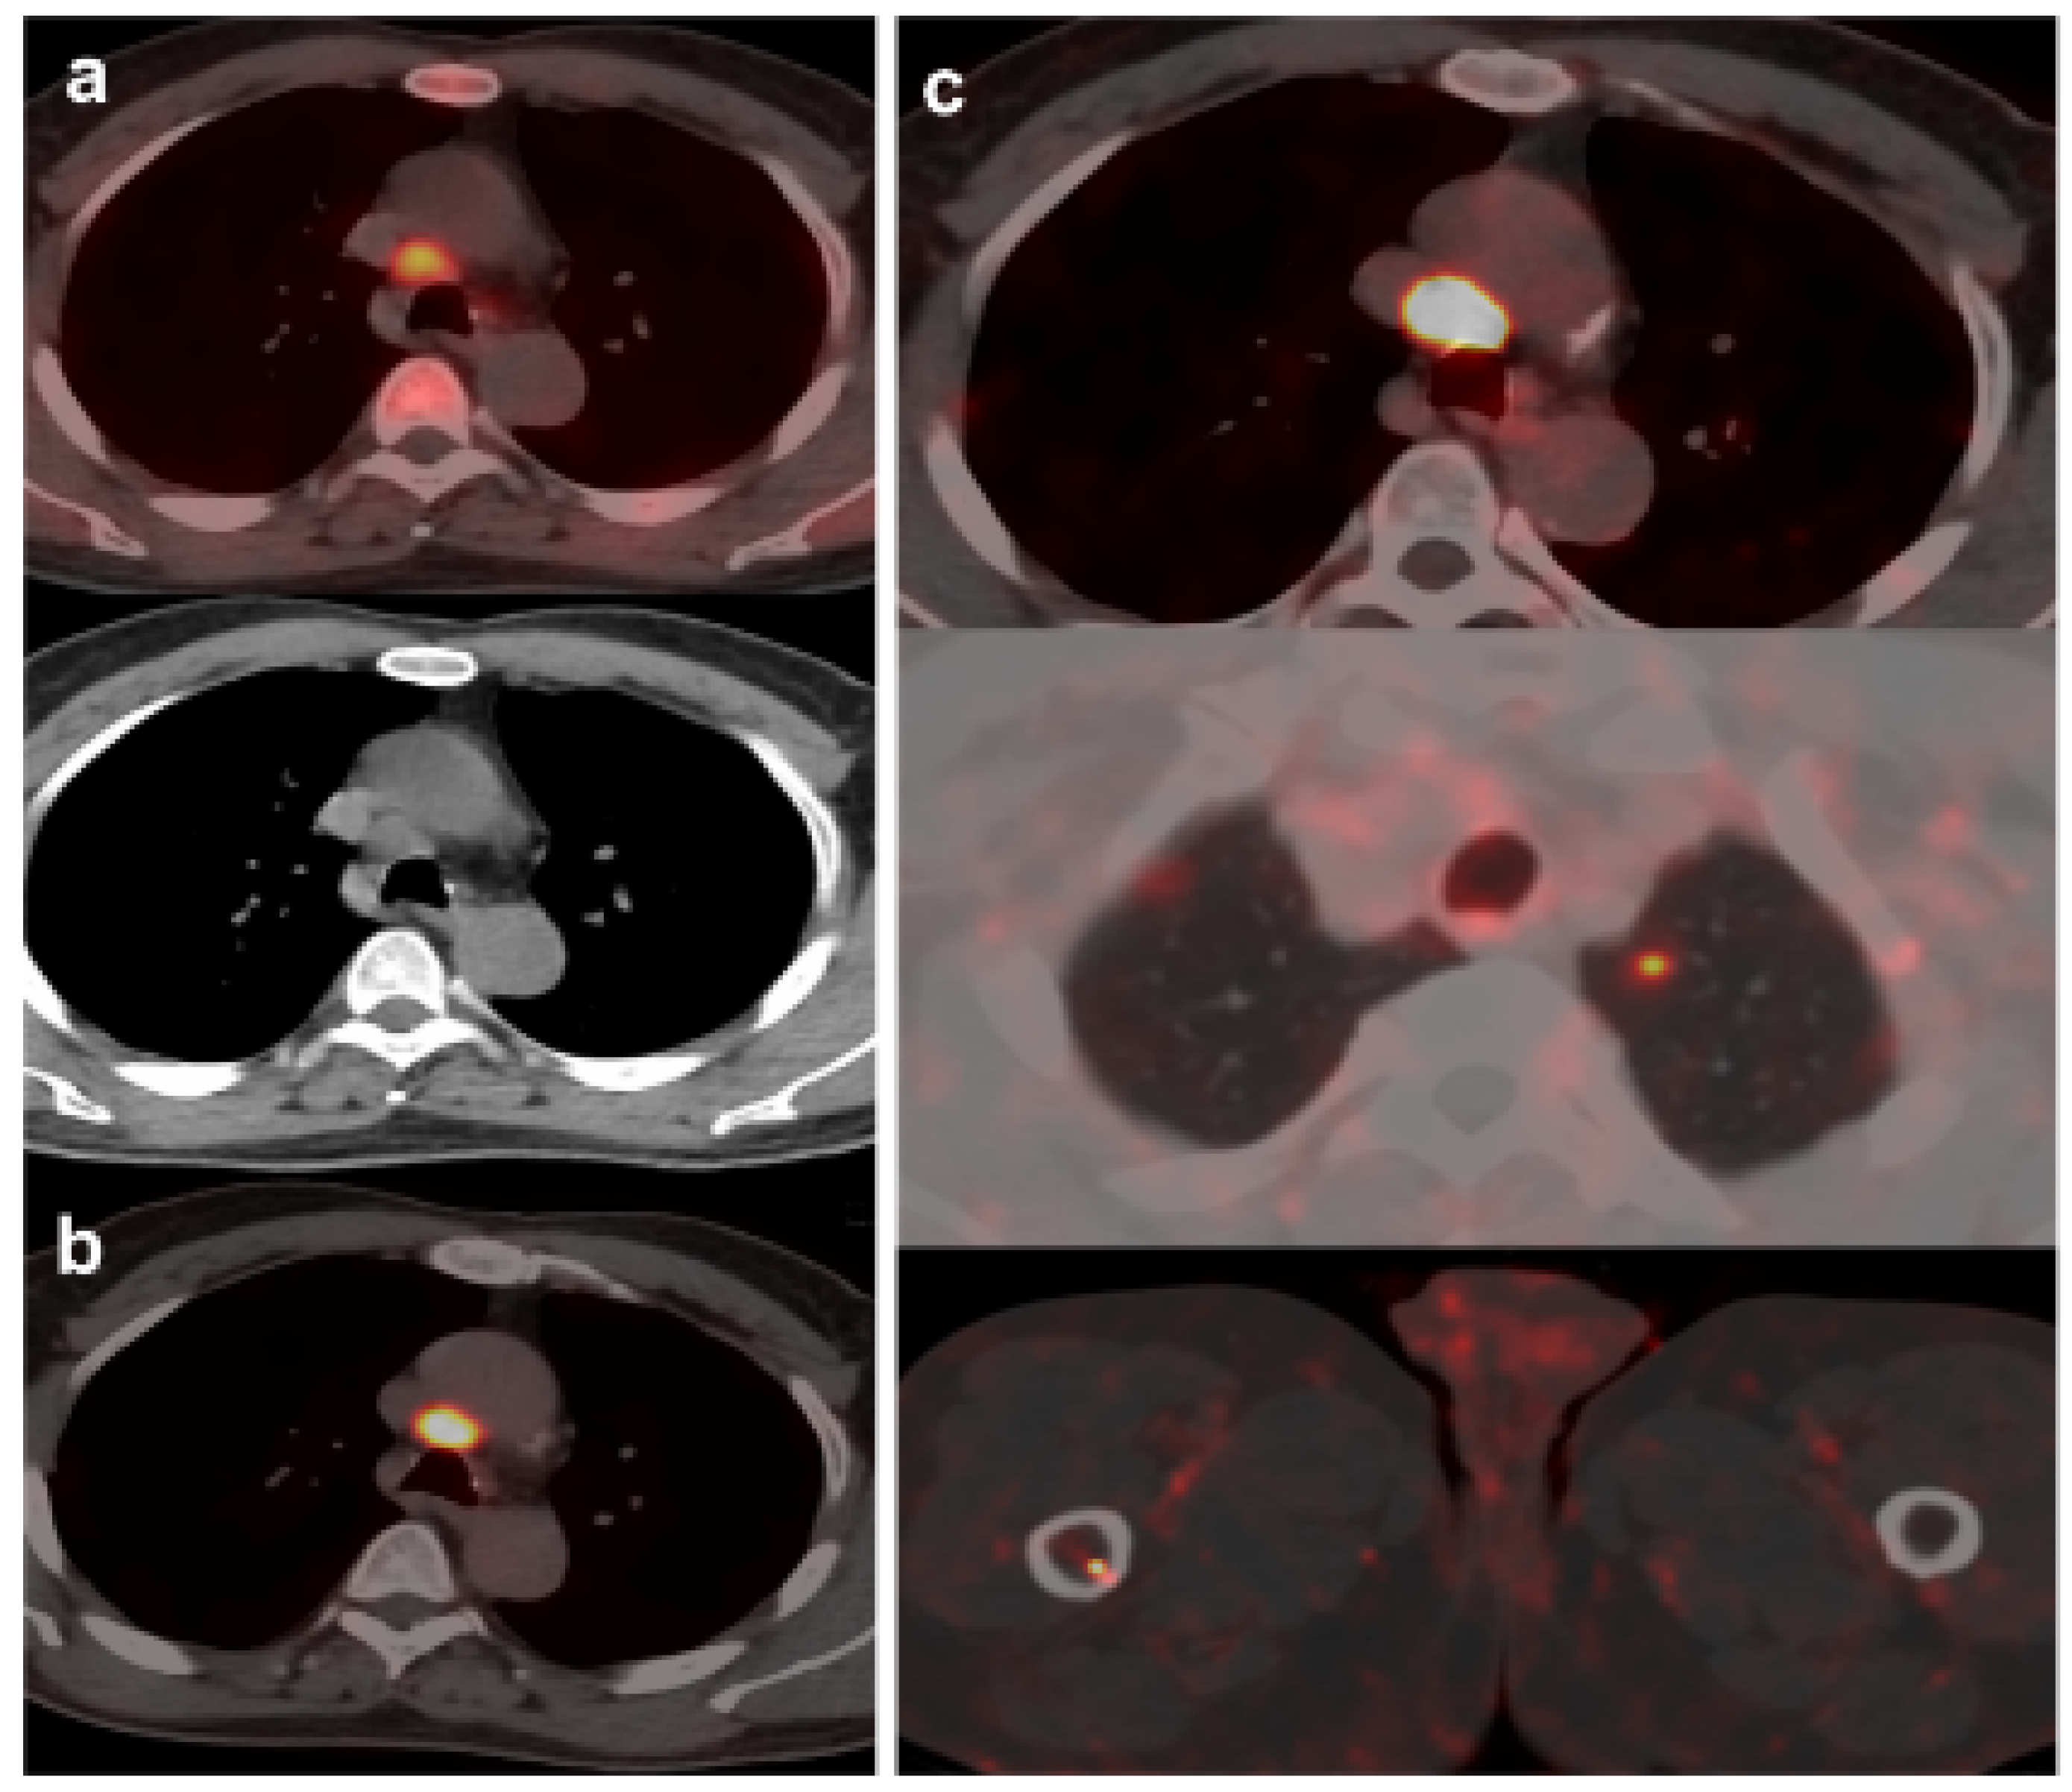

Figure 3.

55-year-old patient. Gleason 8 PCa treated with RP. First BCR treated with prostate fossa radiotherapy. Second BCR (PSA: 0.84 ng/mL, PSAdt 5.99 months, PSAvel 0.07 ng/mL/month). [18F]F-choline-PET/CT negative (a). [18F]DCFPyL-PET/CT (b), time window of twenty days, revealed two right external iliac lymph nodes metastases (white and yellow arrows). Lymphadenectomy was decided (escalation), without histopathological confirmation of malignancy. In follow-up, PSA progressed (2.07 ng/mL) and an additional [18F]DCFPyL-PET/CT (c) showed exactly same lymph nodes (white and yellow arrows). SBRT was administered decreasing the PSA level, reclassifying [18F]DCFPyL-PET/CT results as true positive.